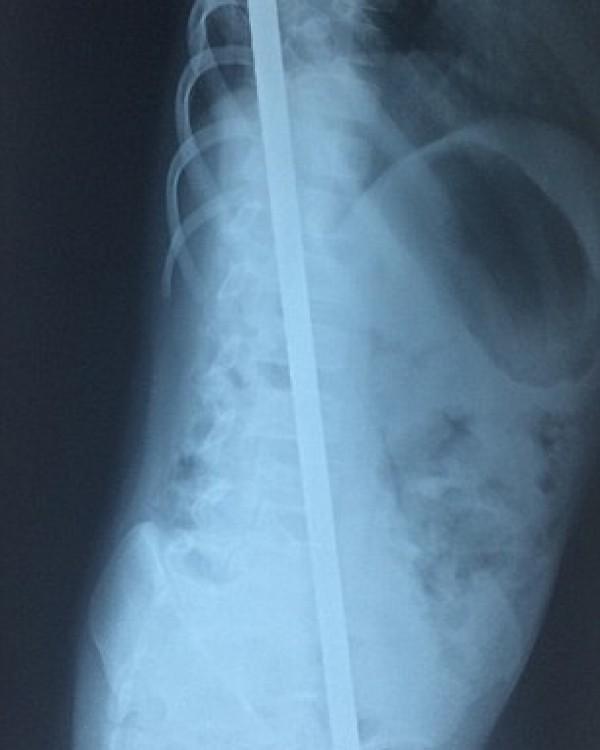

Η βέργα τον διαπέρασε από άκρη σε άκρη. Μπήκε δίπλα από τα γεννητικά του όργανα δίχως να τα πειράξει και βγήκε πίσω από την πλάτη ψηλά, δίχως πάλι να πειράξει κάποιο άλλο ζωτικό εσωτερικό όργανο.

Ο δρ Ρατζιβ Σιγνκ επικεφαλής της ομάδας, είπε πως όταν είδε τον μικρό δεν πίστευε πως θα καταφέρει να τον σώσει. Το χειρουργείο διήρκησε περισσότερες από 6 ώρες. Οι γιατροί πόντο πόντο αφαιρούσαν την βέργα, και προσπαθούσαν να μην πειράξουν κάποιο ζωτικό όργανο.